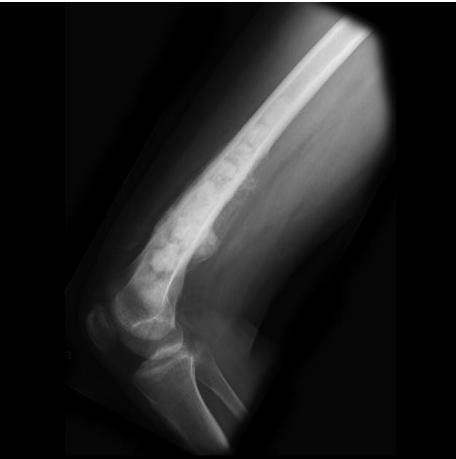

AP lat x-ray

- Site: multiple small Right femu, metaphysis, ddiaphysis

- Size: varying sizes lesions on humerous

- Matrix: Multiple lesions, mixed

- Zone of transition: wide zone transition,

- Bone effect: cortical destruction, periostea reactions

- Soft tissue: periosteal reaction

malignant